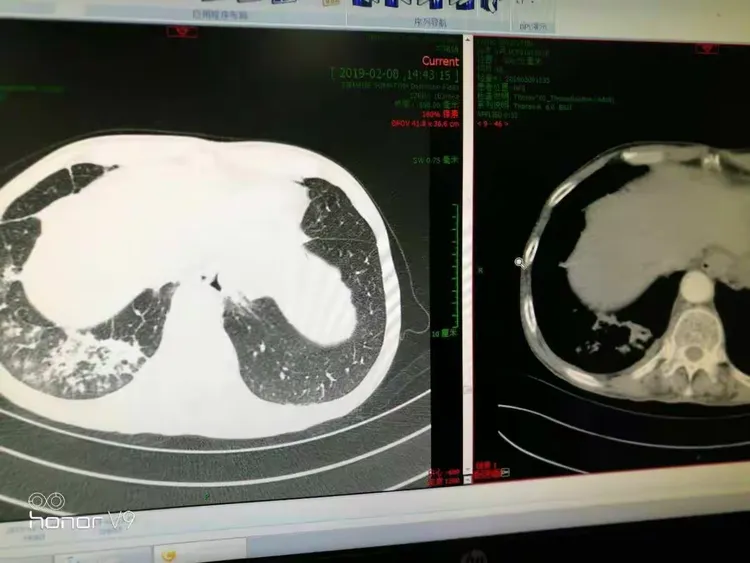

这个月的复查结果糟透了,肺上肿瘤疯长,已经发生了一次咳血。现在没有[s0]射波刀后肿瘤会消失吗[s1]是不是做了肺部穿刺就一定是肺肿瘤或者肺癌?[s2]图片[s3]肺上长肿瘤严重吗 小红书[s4]肺上良性肿瘤怎么办才能消除[s5]确诊为肺癌晚期。医生告知王阿姨,肿瘤发展较快,手术治疗的机会不大。[s6]后,医生的诊断结果让所有人震惊——是肺部恶性肿瘤,且已经是晚期了。[s7]右肺尖肿瘤,16个月迅速长大[s8]吸烟30年,虽已戒烟5年,但这个患者的肺黑得吓人,肺上的恶性肿瘤更加触目惊心![s9]岳母肺部肿瘤病情演变[s10]肺部肿瘤[s11]新方法可能减少肺部肿瘤的生长[s12]微信图片_20190404112215.jpg[s13]胸部肿瘤综合治疗之一肺癌篇~~~科大二附院胸外科胡举副主任医师治疗体会[s14]考虑肺部肿瘤[s15]肺部的恶性肿瘤[s16]肺部肿瘤[s17]右肺上叶肿瘤,穿刺难度大,患者高龄基础疾病多,手术中并发症风险大。[s18]麻烦给看一下我的肺部有肿瘤吗?谢谢了?[s19]肺上肿瘤切除手术好做吗(肺部肿瘤位置尴尬)(1)[s20]肺部巨大肿瘤[s21]少见!6厘米巨大肺部肿瘤—兖矿新里程总医微创切除![s22]查发现患者肺部也有一个肿瘤,考虑患者原发肿瘤在肺部,脑部是转移瘤。[s23]右肺上叶贴水平裂的肿瘤,手术切除范围的考量(病例回顾)[s24]肺部长肿瘤的症状[s25]这是一名35岁女性,左肺上叶将近4厘米的肿物,没有任何症状,查体时才发现,4厘米的肿瘤都没有临床症状,还是很可怕的。腔镜下切除,淋巴结应该不至于有转移,还是略偏早期,但术后是需要靶向药物治疗或者化疗的,尽量降低复发概率。所以,肿瘤不能等有了症状再就诊,分期晚了医生也没有办法。[s26]以前照片[s27]患者高龄基础疾病多,手术中并发症风险大。术前ct见右上肺肿瘤术中操作[s28]肺肿瘤影像大汇总,看完深刻理解[s29]发展,甚至肺上的肿瘤已经缩小了百分之四十,于是在2019年1月3日出院了。在进行了四个疗程的治疗后,[s30]肺上长肿瘤严重吗 mip.haodf.com[s31]肺上长肿瘤严重吗 来自网易[s32]右肺尖肿瘤,16个月迅速长大[s33]肺肿瘤有哪些危害[s34]肺肿瘤[s35]肿瘤标记物虽然是正常的,但是咳嗽原因不明,ct却发现肺上长了肿物.[s36]肺部恶性肿瘤需要手术吗能治好吗[s37]肺上长了肿瘤必须要做穿刺检查吗?[s38]肺部肿瘤能治好吗[s39]